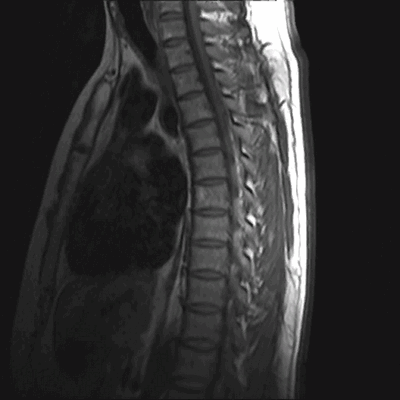

Ведущими в МРТ позвоночника всегда являются сагиттальная (вдоль тела) а аксиальная (поперечная) плоскости, дополнительной может быть корональная (фронтальная) плоскость. Физические основы МРТ и получение МРТ изображения изложены в наших статьях, однако, они предназначены для подготовленного читателя. Разглядывая МРТ изображение позвоночника, Вы увидите, что спинномозговая жидкость (ликвор) на одних из них светлый (почти белый), на других, наоборот, темный. Так можно различить Т2-взвешенные и Т1-взвешенные МРТ изображения. Очень важно понимать, что это не негатив и позитив, а МРТ изображения, зависимые от разных физических характеристик, и потому несущие в себе разную информацию. На снимке (вернее сказать, отпечатке) или на CD диске, сняты или записаны серии однотипных по способу получения МРТ изображений позвоночника. Срезы идут друг за другом, например, справа налево в сагиттальной плоскости. Обычно для облегчения понимания где проходит данный срез в углу картинки дается референтное изображение, оно показывает линию этого МРТ среза в другой, перпендикулярной ему плоскости. Иногда делается дополнительное референтное МРТ изображение на котором показаны все срезы с их нумерацией. Зазор между срезами меньше 1 мм или вовсе отсутствует. Толщина среза выбирается оптимальной в зависимости от исследуемого отдела позвоночника, плоскости и МРТ аппарата. Обычно при МРТ позвоночника она 3-4 мм. В любом случае, выбираемый оператором или врачом протокол МРТ (то есть набор плоскостей и последовательностей), соответствует задачам данного МРТ исследования. Оценка качества МРТ изображения не может быть осуществлена ни пациентом, ни врачом-клиницистом. Заключение, данное врачом-рентгенологом, подразумевает, что само изображение было приемлимым для выводов. Хотелось бы особо подчеркнуть, что Заключение в конце Описания, выдаваемое пациенту, не является диагнозом, а лишь выводами врача- рентгенолога на основе интерпретации им изображений. Диагноз ставится врачом-клиницистом на основании всех имеющихся медицинских данных - жалоб, клинического осмотра, заключений других специалистов, лабораторных анализов, заключений по МРТ и другим изображениям. При этом расхождения между заключениями по результатам разных исследований явление вполне нормальное.

МРТ позвоночника. Сагиттальная Т2-взвешенная МРТ, срединный срез поясничного отдела. Показана нумерация позвонков, измерения позвоночного канала (черная линия). Т- дуральный мешок с ярким ликвором. L- желтая связка. Sacrum - крестец. D - межпозвоночный диск. Голубым выделен остистый отросток, желтым - тело позвонка, Голубые точки - ход корешков.

После того, как появилась ясность в способе получения МРТ изображений позвоночника, надо понять какие анатомические структуры видны. Счет позвонков ведется разными способами - сверху от зубовидного отростка С2 (осевой позвонок), от бифуркации трахеи Т5 ( пятый грудной, с погрешностью на 1 позвонок) или снизу от L5 (последний поясничный), также не исключена погрешность на 1 позвонок в связи люмбализацией или сакрализацией. Анатомия позвоночника в МРТ изображении представлена в нашей другой статье. На серии сагиттальных Т2-взвешенных МРТ позвоночника видны асе основные структуры, причем удается проследить ход корешков конского хвоста. В поясничном отделе он идет под углом вниз и выходит через межпозвоночное отверстие нижележащего позвонка. Аксиальные (поперечные) МРТ срезы всегда делаются вдоль межпозвоночного диска, то есть с учетом нормальных или патологических изгибов позвоночника. Они наиболее удобны для оценки состояния дугоотростчатых суставов. При МРТ позвоночника в поперечной плоскости МРТ срезы часто делают на разных уровнях для лучшей визуализации состояния корешков по их ходу - в дуральном мешке, затем боковом кармане дурального мешка, далее в межпозвоночном отверстии и, наконец, после выхода из него. Таким образом, в поперечном МРТ срезе позвоночника через межпозвоночное отверстие на поясничном уровне можно видеть отрезки сразу двух корешков - вышележащего на выходе из отверстия, и нижележащего в боковом кармане.